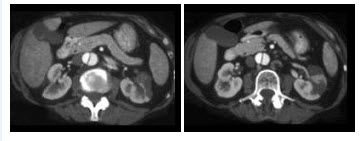

15、单项选择题

如图所示,这两个时相提示()

A.肾细胞癌

B.动静脉瘘

C.肾窦对比剂溢出

D.以上都有可能

E.以上都不是

点击查看答案

本题答案:微信扫下方二维码即可打包下载完整带答案解析版《★放射医学(医学高级)》或《放射医学(医学高级):CT》题库